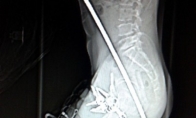

• 世界最诡异的X光片!撬棒刺头链锯穿胸匕首插头

游戏新闻 2014-04-10 15:47:49

拍X光片现在已经成为医院非常常见的诊疗手段,但有时候医院遇到的一些案例简直让人匪夷所思。安徽合肥,一名建筑工人从2.4米高的脚手架上失足落下,从臀部到胸口被一根钢筋穿透,生命垂危。他的工友们立即将他送到医院救治,他后来被抢救了过来,大难不死。这张胸部透视片上可以看到这名患者詹姆斯·瓦伦丁(James Valentine)的脖子到胸腔位置有一个电锯的锯链。当时瓦伦丁正和同事们一同在伐木,突然电锯的链条断裂并反弹回来,切穿了瓦伦丁的胸腔,他被送往医院。阿富汗。这把匕首扎入了一名仅有10岁大的男孩的头部,经过手术之后被取出,并在医院接受后续治疗。这名不幸的男人被一根撬棍刺穿头部:一名中国的69岁老人被人送往医院,X光片显示他的头顶被钉入了3根钉子。医生紧急手术将钉子取出。但老人坚称钉子是自己钉入的,但医